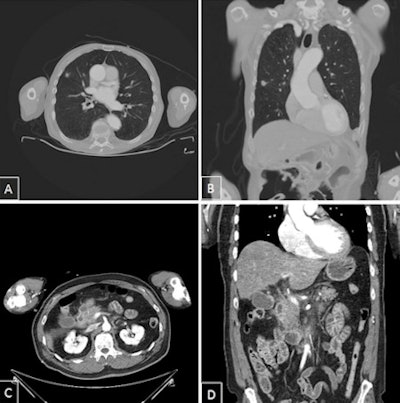

As part of a larger clinical study on whole-body CT, radiologists in Berlin have now taken a closer look at these secondary findings. The radiologists reported the first results during RöKo 2016. For example, of the total of 518 patients who underwent a whole-body CT scan between September 2014 and April 2015, almost 300 (57.9%) presented with secondary findings. Every 10th patient required immediate treatment.

"Among them were cases of previously undetected acute pneumonia and inflammation of the pancreas, as well as tumors of the lung and brain," Kahl said.